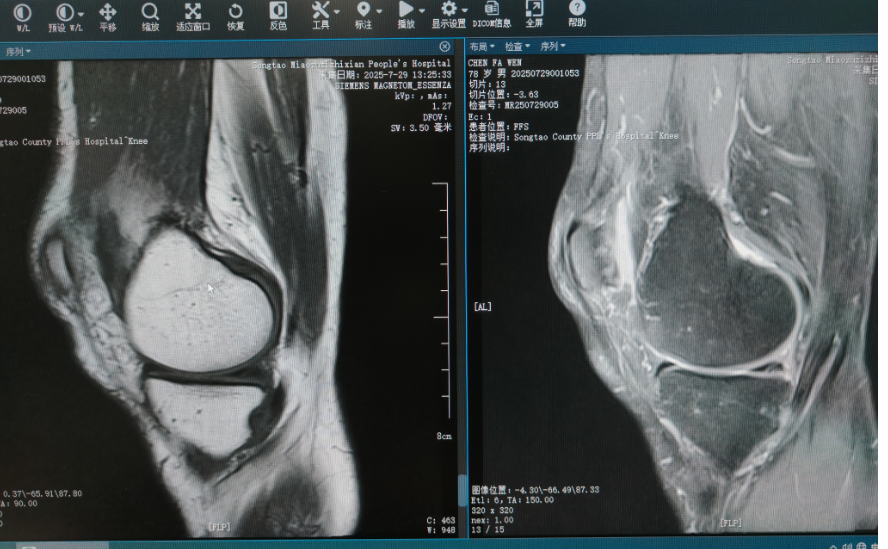

MRI显示损伤部位

78 岁的老人一年前出现了双膝关节疼痛,右侧尤为明显,活动及上下楼梯时痛感加剧,休息后可缓解。2 个月前,右膝关节疼痛突然加重,伴随深蹲受限及弹响,严重影响生活,患者家属带着老人来到县人民医院关节外科就诊时,老人步态不稳,行走时疼痛明显。恰好驻点帮扶的李朗明医生接诊了这位患者,他仔细进行骨科专科检查,结合影像学检查,诊断为双膝半月板损伤、双膝原发性骨性关节炎。随后,李朗明与科室团队研究治疗方案,结合患者病情,科室决定先解决右膝关节问题。在详细告知手术替代方案并征得患者及家属同意后,确定实施关节镜下右侧膝关节半月板成形 + 滑膜切除术。

术前,医疗团队认真分析影像学资料,明确损伤部位与手术方案,术中团队精准操作,术后在护理团队的精心照护下,患者恢复良好,行走稳健。